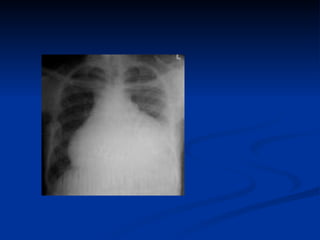

PERICARDITIS Radiografía de tórax Pruebas de laboratorio VES-PCR-BHC-FR-ANA Ecocardiografía Biopsia pericardica

PERICARDITIS Radiografía detórax Pruebas de laboratorio VES-PCR-BHC-FR-ANA Ecocardiografía Biopsia pericardica